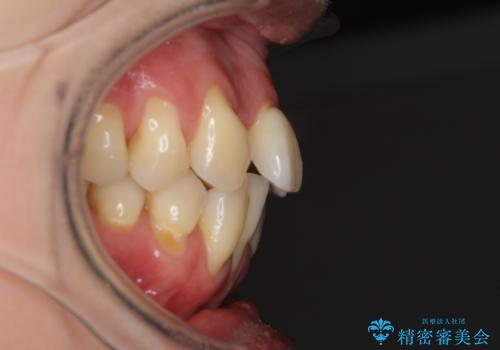

通常であれば、上下顎左右小臼歯各1歯の合計4本を抜歯しますが、歯肉退縮の著しい下顎前歯を抜歯して欲しいという患者様の強い希望により、上顎のみ左右小臼歯2歯を、下顎は前歯を1歯を抜歯することとしました。

抜歯する歯を変更したため奥歯の咬合はアンバランスとなりましたが、前歯は綺麗に整い、歯肉退縮も回避できました。